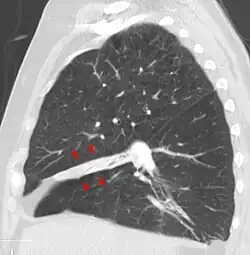

Atelectasis of the middle lobe on a sagittal CT reconstruction.

Atelectasis is broadly categorized into obstructive (resorptive) and non-obstructive types. It may be further classified as an acute or chronic condition. In acute atelectasis, the lung has recently collapsed and is primarily notable only for airlessness. In chronic atelectasis, the affected area is often characterized by a complex mixture of airlessness, infection, widening of the bronchi (bronchiectasis), destruction, and scarring (fibrosis).